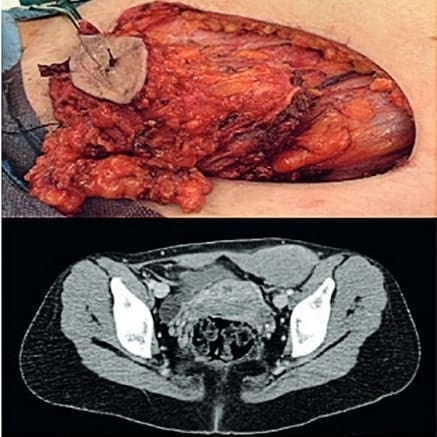

Figura 2. Caso clínico 2, femenina de 32 años, en la parte superior se muestra la masa resecada,

en la parte inferior se observa la resonancia. Fuente: Hospital Miguel Servet, Servicio de cirugía general.